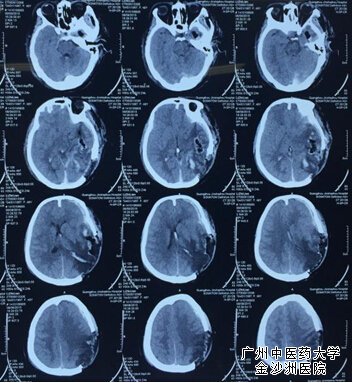

8月5日15点~18点经过3小时麓战,清除颅内血肿、艰难细致的止血,手术成功,病人苏醒。让人始料未及的是,就在大家小憩之时,病人再次发生颅内出血、脑疝昏迷,惊险迭起如不及时手术将危及病人生命,于2015年8月6日再次手术颅内血肿清术,术后病人清醒,但很快病人又进入嗜睡状态,这意味着再次颅内出血,急诊复查头部CT证实颅内再次出血,而且病情极为凶险。院方立即组织广州市神经外科权威专家会诊,专家会诊一致意见“尽力抢救,但存活的可能性渺茫”;面对专家的会诊意见和家属绝望的恐慌,周强教授面对的社会压力以及家属可能不理解而出现的过极行为,决然未虑决定再次手术抢救,“只要有一线希望,都要百分之一百的努力”,这是他的行医准则。他耐心细致地和家属沟通,最终家属理解了只有再次手术亲人才有生存可能。

在广州中医药大学金沙洲医院刘文胜院长的支持领导下,组织医院麻醉科、手术室、影像科、检验科、药房、输血科及供应室等科室通力配合,于2015年8月6日凌晨4:00再次行开颅血肿清除术,经6小时艰辛的手术,成功了!术后病人安返病房,麻醉期后病人清醒了。四天三夜,先后经历四次手术,虽然病人颅内出血得到控制,但是,四次手术及反复颅内高压所引起的肺部感染、应激性溃疡、水、电解质平衡紊乱以及脑水肿、再灌注脑损伤等并发症的处理又考验着王忠诚脑科中心的每一位医护,任何一项并发症都可能危及此病人生命,加之病人术后还有出现偏瘫、失语及双目失明的可能性,让周强教授和家属都寝食难安。“病人四肢能动了”、“病人能遵嘱活动了”、“病人能看到东西了”,“病人能说话了”,一个个喜讯每天都回荡在脑科中心,就连脑科中心的其他住院病人和家属都为之兴奋和喜悦。

第一次术后血肿                                   第二次术后血肿

第三次术后血肿                                                  第三次术后血肿清楚术后